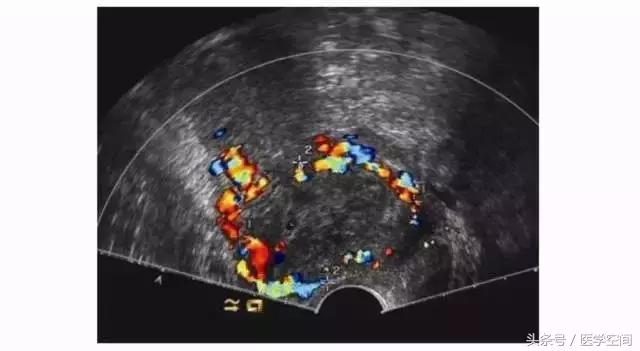

又分为两种类型,第一种为宫腔内见孕囊型,孕囊多位于宫腔下段(较大孕囊可充满整个宫腔),但孕囊部分种植于剖宫产子宫瘢痕处,彩色多普勒超声(CDFI)检查瘢痕部位常可见较丰富血流信号(见图2);第二种为瘢痕部位包块型,子宫剖宫产瘢痕处未见孕囊,可见不均质低回声包块,其周边常可见较丰富血流信号(见图3)。不典型CSP容易漏诊及误诊。

图2不典型CSP的超声表现

CSP超声漏诊进行了药流或人工流产、CSP自发流产不干净的患者,行超声检查时常表现为子宫剖宫产切口瘢痕处的不均质低回声肿块,CDFI在肿块周边常可探及丰富的血流信号(见图5),脉冲多普勒超声检查可探及低阻滋养动脉血流频谱,经验不足者可能会误诊为滋养细胞肿瘤,继而施以化疗。

图5不典型CSP的超声表现